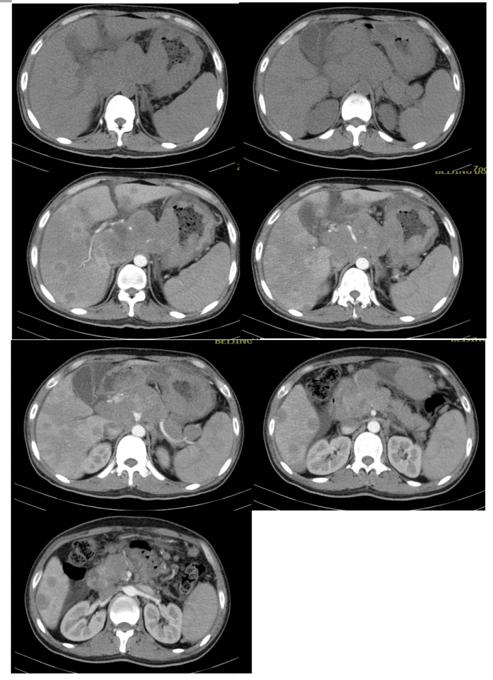

腹部增强CT(如下图一所示):肝脏、胃、腹腔及腹膜后多发淋巴瘤(腹腔、肝门区及腹膜后见多发肿块影.增强后轻度强化,融洽成大块,大小约85X110X97mm,肿块与胰腺关系密切)。2、腹腔少量积液

图一